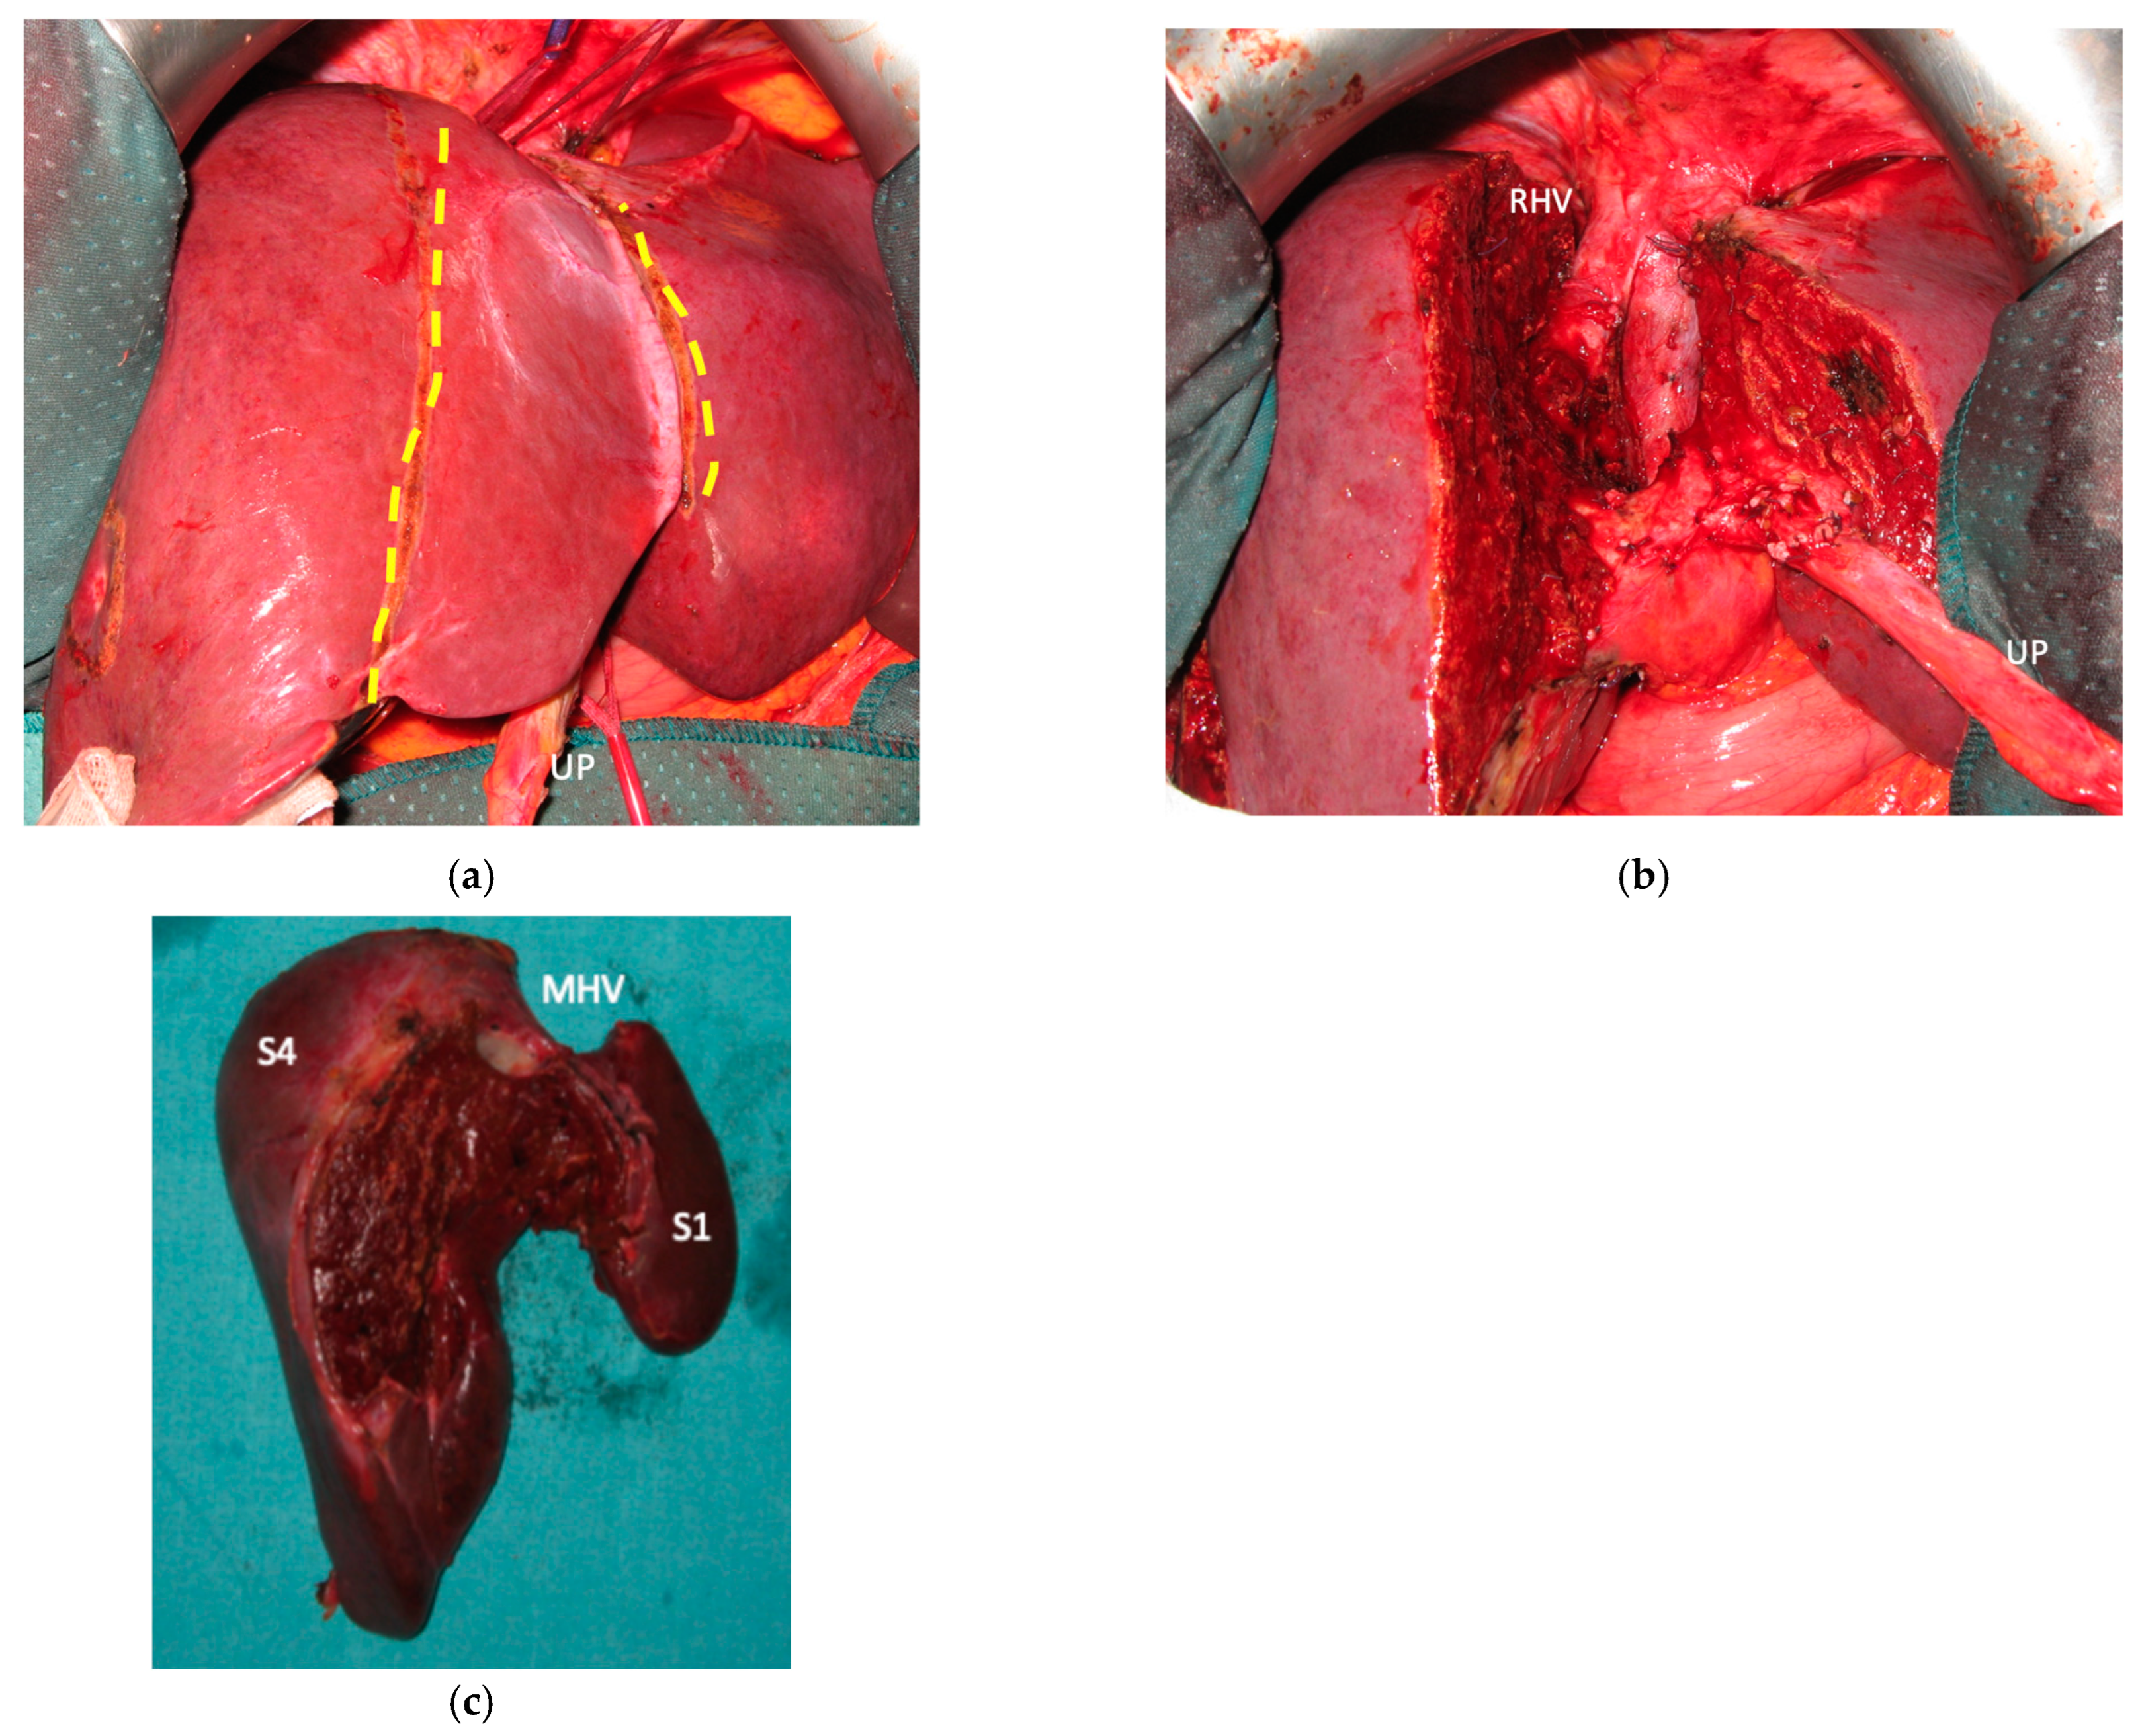

Liver partition was obtained with a major mesohepatectomy in two cases with anatomical resection of S1/S4/S8 (en-bloc with biliary tree in one, see Figure 5).

Two out of eight patients with unresectable disease relapse are still alive although with evident disease: one patient 18 months after e-ALPPS performed as a “liver first” strategy for 27 synchronous CRLMs with left colon adenocarcinoma and interaortocaval lymph nodes, then followed by a left hemicolectomy and interaortocaval lymphadenectomy, who experienced an extrahepatic recurrence 3 months after surgery; and one patient 38 months after a major MLP associated with a three-duct jeujunostomy (performed for two CRLMs infiltrating the confluence of left and right bile ducts up to S8 bile duct and with modest dimensional increase of CRLM after 47 cycles of FOLFIRI + Bevacizumab across several reintroductions, Figure 5), with hepatic and extrahepatic recurrence 12 months after surgery.

Figure 5. This is a case of liver partition obtained with a major mesohepatectomy performed for CRLM that behaves as biliary cancer infiltrating the confluence of left and right biliary ducts up to S8 duct; this is a highly challenging location for CRLMs at high risk of worsening patient’s quality of life and hampering chemotherapy administration due to jaundice; for this reason, liver resection was performed despite a modest dimensional increase of CRLMs after several courses of FOLFIRI + Bevacizumab administered over three years and after an initial complete radiological response. (a) Intraoperative field with the identification of the two liver transection lines for liver partition (yellow dotted lines). (b) Liver partition at the end of resection of S1/S4/S8 en-bloc with extrahepatic biliary tree resected up to left duct, S5 duct and posterior duct. Three-duct jeujunostomy was performed. Thirty-eight months after liver partition, the patient is under chemotherapy treatment (no jaundice) with stable and asymptomatic extrahepatic and hepatic recurrence. Abbreviations: CRLM: colorectal liver metastases; S: segment; RHV: right hepatic vein; UP: umbilical portion.